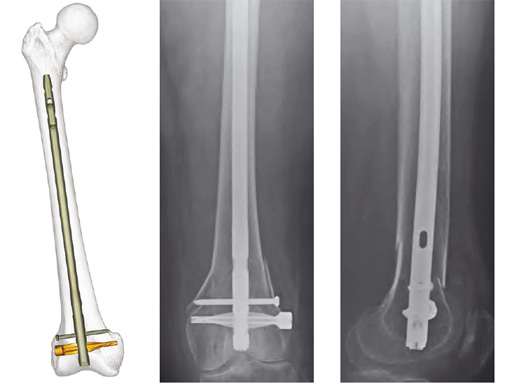

Expert Retrograde / Antegrade Femoral Nail (R/AFN)

The R/AFN is a cannulated intramedullary nailing system for the treatment of fractures of the distal femur and/or diaphyseal fractures in which a retrograde approach is indicated. The R/AFN also enables fixation of fractures of the femoral shaft with an antegrade approach through the piriformis fossa.

The R/AFN has a universal design for the right or left femur with an anatomic bend (1.5 meter radius of curvature). The locking options include spiral blade and standard locking. Proximal locking holes are optimized for the lengths of the nail. The use of a locking end cap secures the spiral blade or the most distal locking screw in place, creating an angular stable construct which is advantageous for fixation of fractures involving the femoral condyles.

The R/AFN is available in shaft diameters from 9 mm to 15 mm and lengths from 160 mm to 480 mm, in 20 mm increments. Lengths from 160 mm to 280 mm are designed for retrograde insertion only. Lengths from 300 mm to 480 mm can be used for both antegrade and retrograde insertion. 5.0 mm and 6.0 mm Ti locking screws are available with a T25 StarDrive recess.